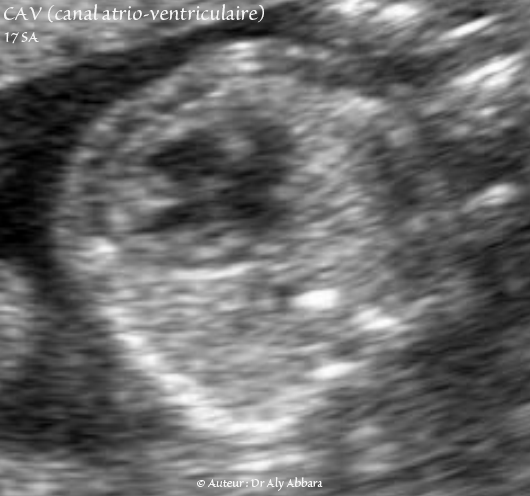

Canal atrio-ventriculaire complet - CAV - Vidéo et image animée échocardiographiques - 17 SA - القناة الأذينية البطينية

Canal atrio-ventriculaire complet 17 SA - CAV - Vidéo et image animée échocardiographiques - القناة الأذينية البطينية

• Vidéo et image animée échographiques cardiaques montrant la présence de :

• un canal atrio-ventriculaire (CAV) complet.

• une valve atrio-ventriculaire (VAV) commune à une ouverture diastolique satisfaisante vers deux ventricules équilibrés.

• une communication inter-auriculaire (CIA) de type ostium primum large aboutissant à la constitution d'une oreillette unique ou quasi unique.

• la valve de Vieussens battant dans le secteur gauche de l'oreillette unique.

• une communication interventriculaire (CIV) très large ; il s'agit d'une communication de type de CIV d'admission.

• Fœtus âgé de 17 SA trisomique 21.